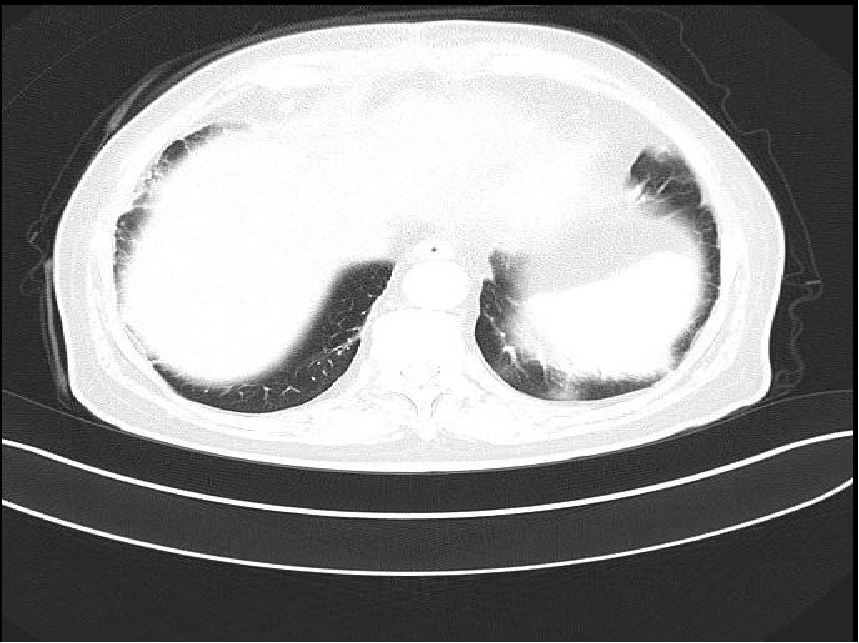

2018-07-17复查胸部CT:

胸部CT扫描示:

左肺上叶实性结节,请结合病史,除外转移。

纵隔多发稍大淋巴结。

左肺上下叶及右肺中叶发小结节,随诊复查(6月)。